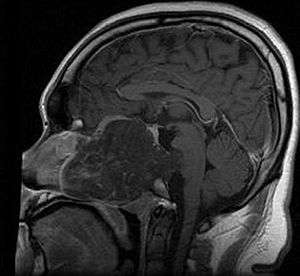

Chordomas can arise from bone in the skull base and anywhere along the spine. The two most common locations are cranially at the clivus and in the sacrum at the bottom of the spine.[1]